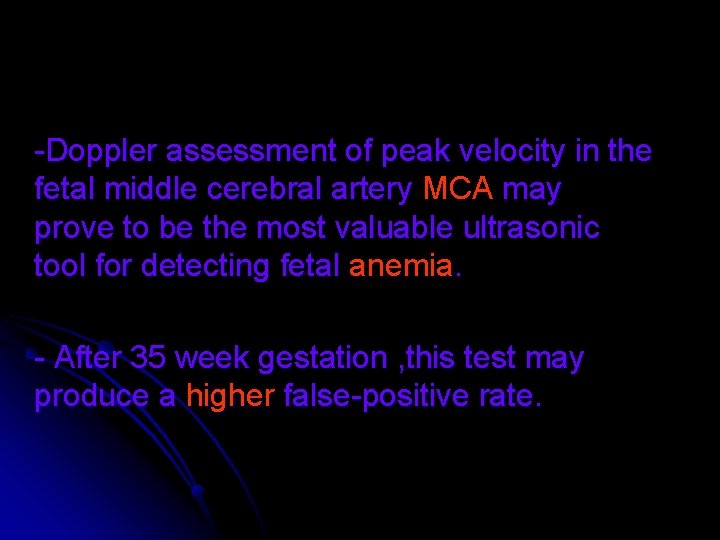

-Doppler assessment of peak velocity in the fetal middle cerebral artery MCA may prove to be the most valuable ultrasonic tool for detecting fetal anemia. - After 35 week gestation , this test may produce a higher false-positive rate.

Circle of Willis at 24 weeks’ gestation. The appropriate place to measure peak systolic velocity is marked. ((arrow))